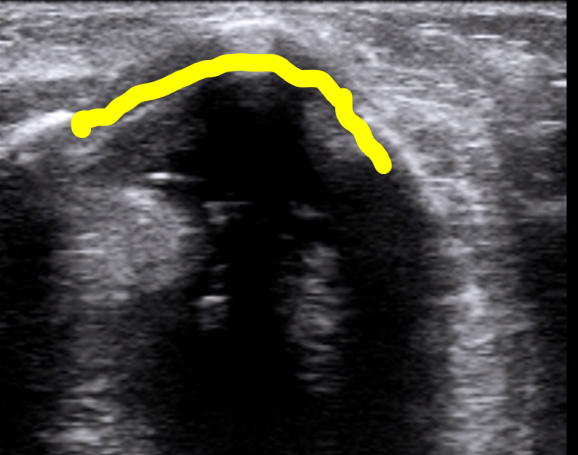

5. 环状软骨平面的扫查

在环甲膜扫查平面我们就发现了环状软骨和气管软骨。选择横向切面,可见一马蹄形低回声伴高回声气体黏膜的分界。图9右上绿色区域和右下绿色区域分别为横切面和纵切面的环状软骨。横切面环状软骨两侧的距离为环状软骨的直径。

图片

图9  环状软骨平面扫查